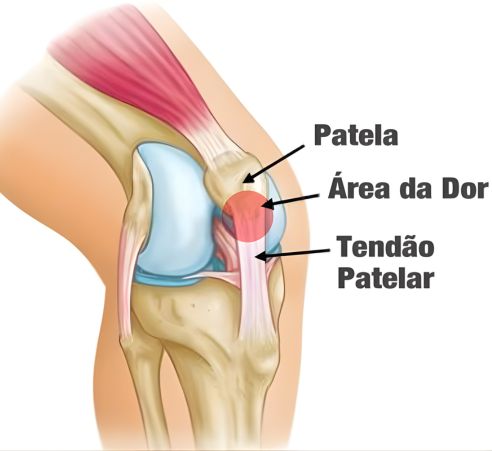

Você costuma sentir uma dor incômoda na parte da frente do joelho, logo abaixo da patela (a “rótula”), especialmente após praticar esportes que envolvem saltos ou corridas? Se essa dor persiste e parece piorar com a atividade, você pode estar sofrendo de Tendinite Patelar, popularmente conhecida como “Joelho de Saltador”. Essa condição dolorosa afeta o tendão que conecta a patela à tíbia, limitando o desempenho e impactando a qualidade de vida se não tratada adequadamente.

Para entender a dor, imagine o joelho de saltador não como uma lesão súbita e aguda, mas sim como um desgaste progressivo da cartilagem atrás da patela. A cartilagem, que deveria ser lisa e uniforme, torna-se amolecida, irregular ou com fissuras. Com o tempo, o atrito excessivo entre a patela e o fêmur (o osso da coxa) gera inflamação e dor, podendo levar a danos mais severos se não abordada.

No início, a dor pode ser leve e surgir apenas após o esforço físico. Com a progressão da condição, o desconforto pode se tornar constante, dificultando tarefas simples como subir escadas, agachar ou levantar de uma cadeira. Além da dor, os pacientes podem notar rigidez local, inchaço leve e sensibilidade ao toque na área inflamada, especialmente ao redor do trocanter maior, onde a bursa fica localizada.